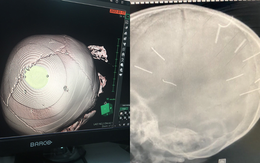

Bác sĩ BV Xanh Pôn chia sẻ về những ngày cuối đời của bé gái bị nhân tình của mẹ đóng 10 chiếc đinh vào đầu

TS. BS Trần Văn Trung thông tin, suốt quá trình điều trị tại bệnh viện, bé luôn trong tình trạng hôn mê, bị tổn thương không hồi phục. Dù đã hội chẩn với các bác sĩ chuyên khoa khác để có phương án phẫu thuật rút đinh cho cháu, tuy nhiên sức khoẻ cháu không đảm bảo nên các bác sĩ chưa thể thực hiện phẫu thuật được.

Ông nội bé gái bị đóng đinh vào đầu: "Bé sức khoẻ yếu nhưng gia đình quyết định phẫu thuật bỏ đinh để dù không được làm người cũng không còn đau đớn"

Dù tiên lượng sức khoẻ của bé gái 3 tuổi bị bạo hành khá yếu, đã không thể ăn xông nhưng gia đình vẫn quyết định đề nghị bác sỹ mổ loại bỏ đinh để bé không còn đau đớn.

Vụ bé 3 tuổi bị nhân tình của mẹ đóng đinh ở đầu: Đáp ứng điều trị kém, tiên lượng dè dặt

Đại diện Bệnh viện Xanh Pôn cho hay, theo báo cáo của bác sĩ điều trị, hiện tại bệnh nhi 3 tuổi bị người tình của mẹ đóng 9 đinh vào đầu đáp ứng điều trị kém, tiên lượng dè dặt.

Sức khoẻ của bé 3 tuổi bị người tình của mẹ đóng đinh vào đầu hiện ra sao?

Theo bác sĩ điều trị cho bệnh nhi Đ.N.A. (3 tuổi, xã Canh Nậu, huyện Thạch Thất, Hà Nội), bệnh nhi vẫn đang trong tình trạng hôn mê.